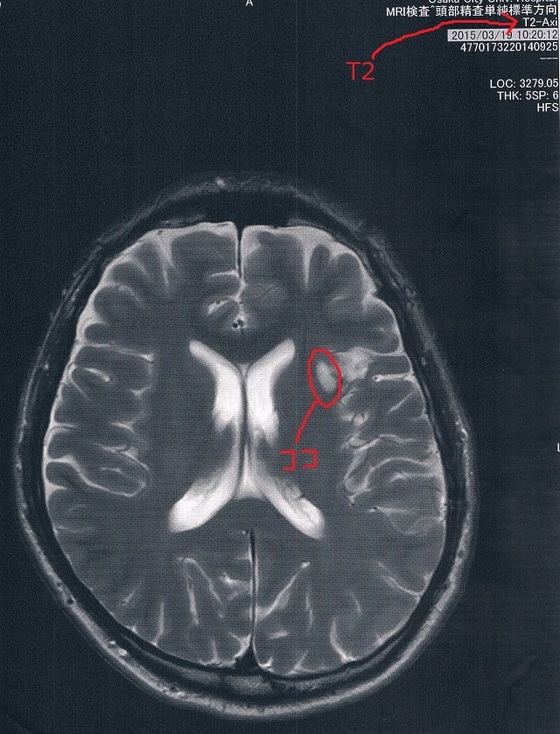

2015/3/19(手術後9か月)のMRI画像

今回2016/3/24(手術後21か月)のMRI画像

今回もらった画像は前回とは画像強調が異なっているので白黒が反転しているところがある。

が、問題の腫瘍の部分は変化が無いので問題なし!

(興味ある人はFLAIRとT2で検索すると、MRIに詳しくなれます。)